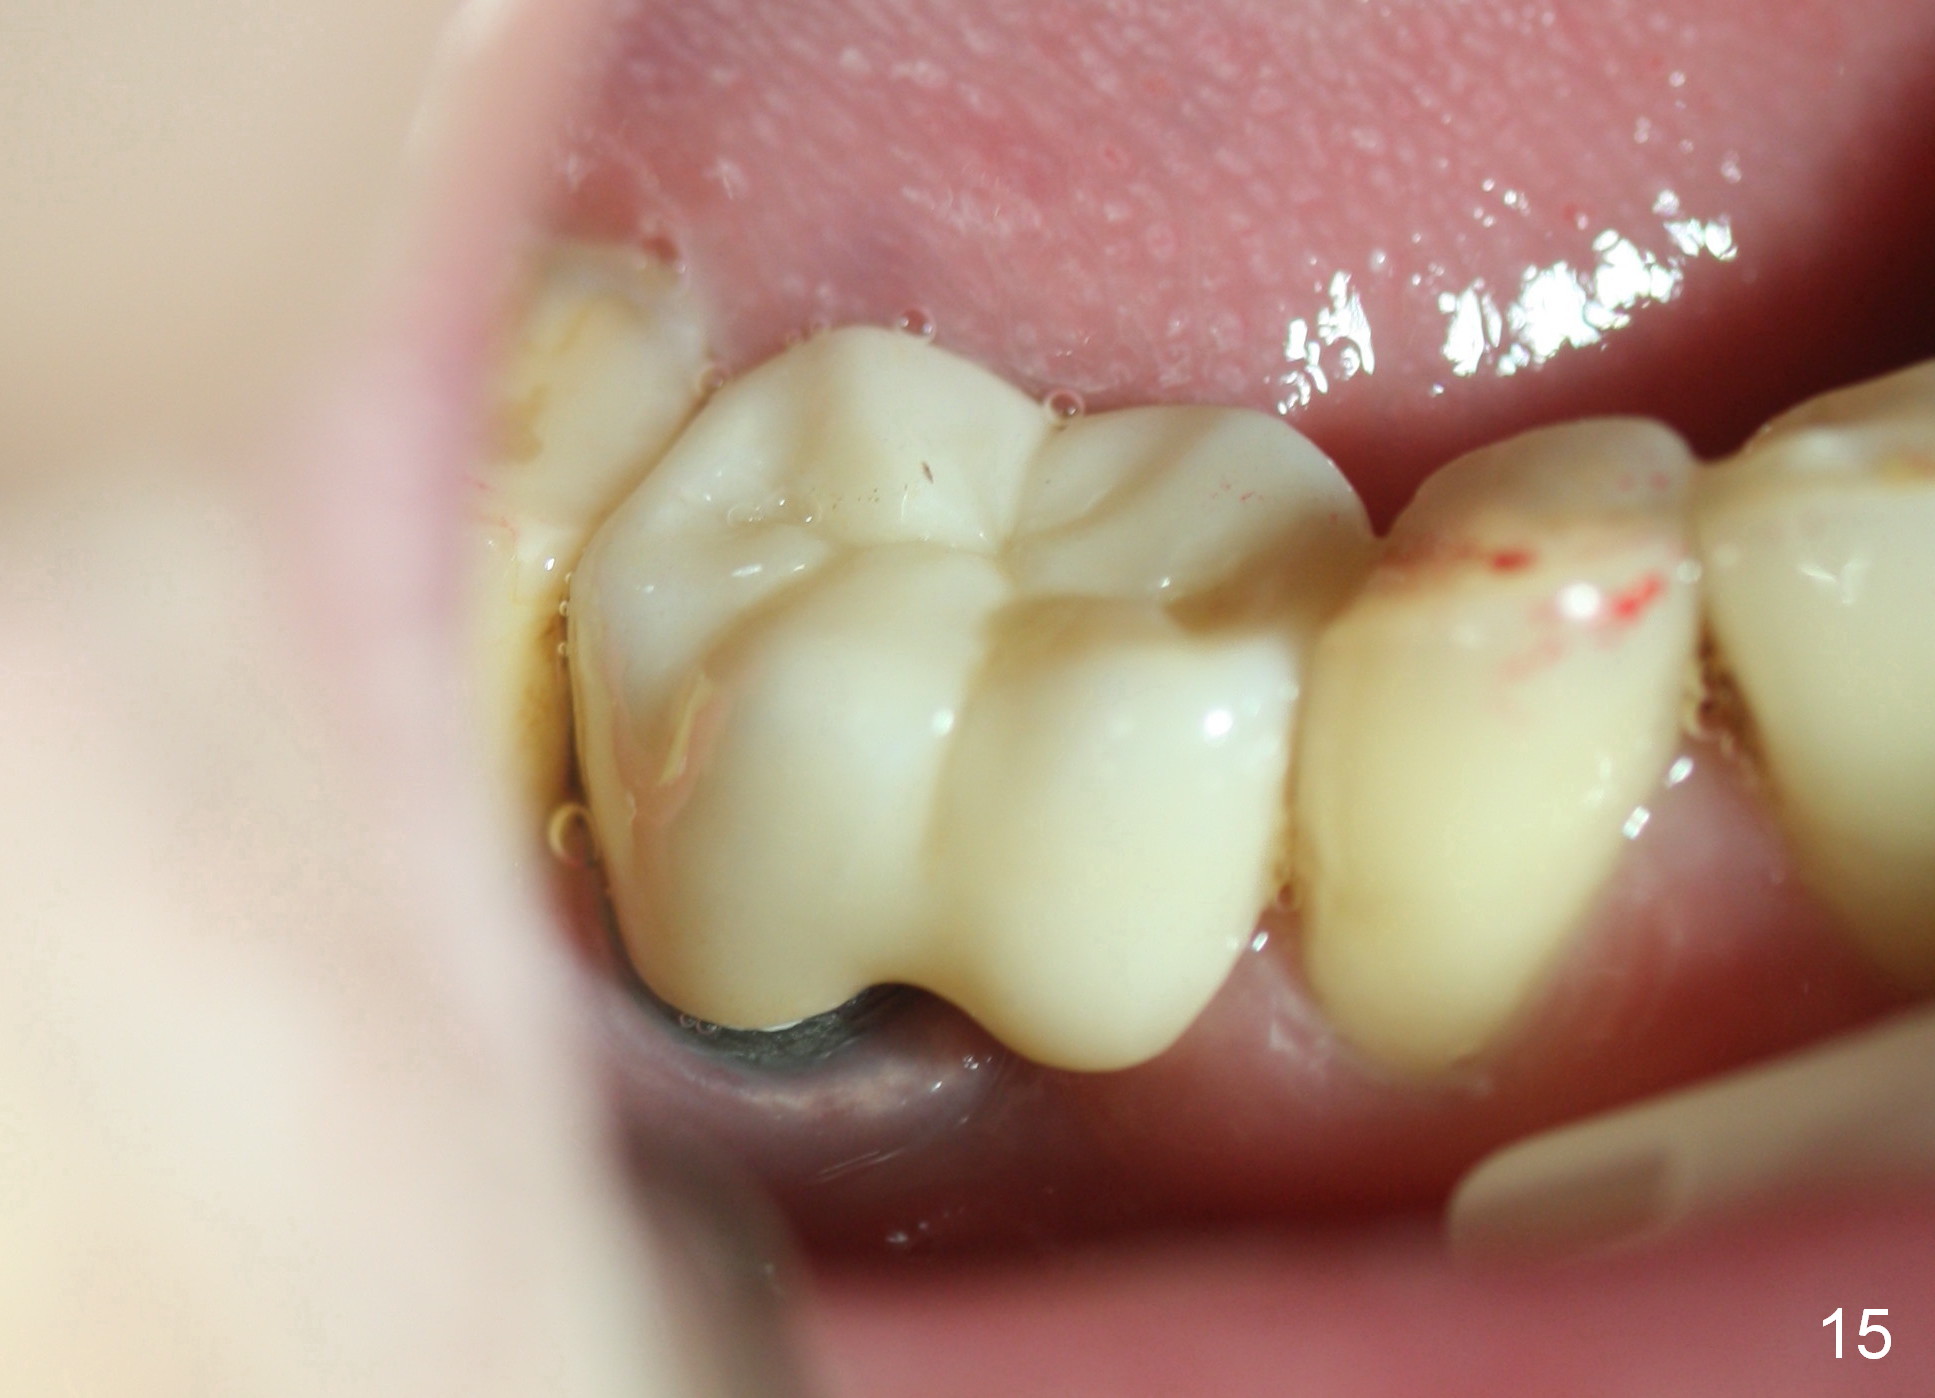

When the perio dressing is removed in office 24 days postop (Fig.9), the rough surface of the implant (R) is exposed buccally. Normally the smooth surface should contact the gingiva (S). Lingually implant/gingiva position is within normal limit (Fig.10). The patient returns for restoration 4 months postop (Fig.11,12). There is bone formation in the mesial socket and new bone appears to have grown toward the implant (Fig.11 <). A straight abutment appears to be in the middle of the edentulous space (Fig.12 A). But it is difficult to seat the crown. Three months post cementation, the patient complains of food impaction mesially (Fig.10 ^), although bone density continues to increase in the mesial socket and there is no mesial coronal thread exposure (*). Retrospectively the implant should be tried to be placed in the septum as much as possible to have a favorable restorative axis (Fig.14). The crown is re-fabricated with larger mesial contact area. It is temporarily cemented because of slightly loose distal contact (Fig.15). A few days later, the patient requests permanent cementation, because although the distal contact is loose, it is easy to remove food. Mesial food impaction is less likely, but it is more difficult to be removed.